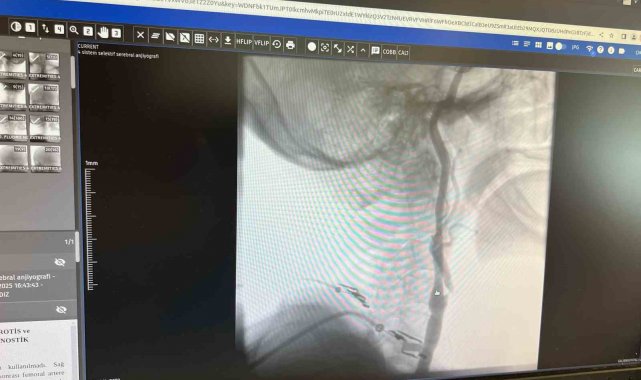

"Boyun damarlarını açma işlemi iki şekilde yapılabilir. Bir karotis endarterektomi dediğimiz ameliyatla bir diğer yöntem ise perkutan girişim dediğimiz stent yöntemiyle açılabilir. Biz kliniğimizde nöroloji ve kardiyoloji olarak bir konsey yapıyoruz. Damarı ciddi tıkalı olan ve buna bağlı felç geçirmiş hastalarda bu konseyde hastaya işlem yapıp yapmama kararı veriyoruz. Verdiğimiz karar çerçevesinde eğer hastaya işlem kararı vermişsek femoral arter dediğimiz kasık arterinden bir şitle 6 ya da 7 F çapında bir şitle ince bir boruyla bu damara giriş yapıyoruz ve boyun damarlarına ulaşıyoruz. Özellikle teller, filtreler ve stentlerle bu damarları açıp hastanın tedavisini gerçekleştiriyoruz. İşlem ameliyatsız olduğu için hastamız ertesi gün rahat bir şekilde problem olmazsa işlemde taburcu olabiliyor bu işlemden sonra. Bu işlemin yapılması için özellikle anjiografinin olduğu girişimsel nöroloji uzmanının ve girişimsel kardiyoloji uzmanının olduğu ve bu konuda yeterli vaka tecrübesine ve deneyime sahip uzmanların olduğu merkezler gerekir. Bunu yapabilmek için belli bir vaka sayısına ulaşmak ve bu konuda tecrübeli olmak gerekiyor. Biz de Manisa Şehir Hastanesi'ndeki girişimsel kardiyoloji ve nöroloji uzmanları olarak bu işlemi kliniğimizde efektif bir şekilde gerçekleştiriyoruz."